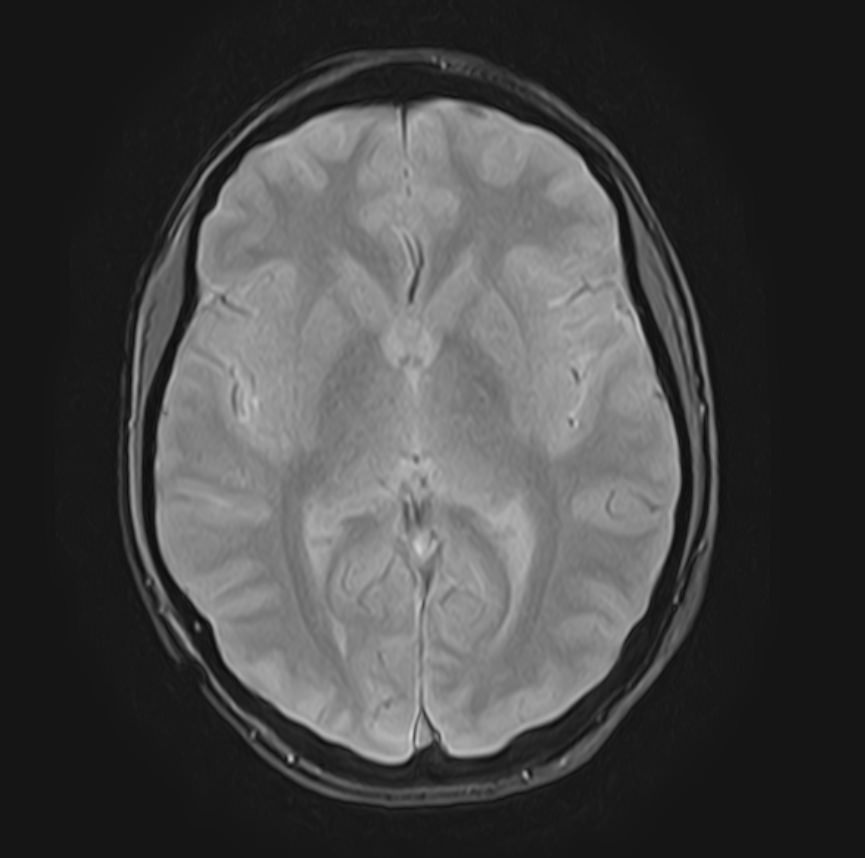

В клинике «Доступная медицина» можно пройти комплексное обследование, включающее в себя несколько протоколов сканирования близко расположенных друг от друга анатомических областей – шейного отдела позвоночника и головного мозга. Метод комплексного обследования оценивает состояние всех структур головного мозга и шейного отдела позвоночника. При этом дополнительные протоколы обследования позволяют визуализировать крупные сосуды шеи и сосудистую сеть головного мозга.

Сканирование проводится на современном высокопольном магнитно-резонансном томографе закрытого типа TOSHIBA VANTAGE TITAN 1,5 Тесла. Магнитно-резонансный томограф производит послойное сканирование исследуемой зоны в разных плоскостях, затем при помощи компьютерных программ преобразует полученные данные в трехмерные изображения. При этом кровеносная система реконструируется как вместе с окружающими тканями, так и отдельно без них.

Стандартная МРТ проводится без использования контрастных веществ. В ряде случаев исследование проводится с внутривенным введением контраста, содержащего соли гадолиния (Омнискан, Магневист и др). Контрастное вещество попадает в кровоток и при сканировании МР-томографом измененные участки становятся лучше видимыми, что помогает в диагностике таких заболеваний, как рассеянный склероз, способствует выявлению опухолевых новообразований и некоторых сосудистых патологий.

• очаги ишемического и геморрагического инсульта, область поражения, признаки отека головного мозга, стадию развития заболевания;

• доброкачественные и злокачественные новообразования, их точную локализацию, стадию развития процесса, проводить динамическое наблюдение за опухолевым процессом на фоне лечения;

• признаки демиелинизирующих заболеваний (рассеянный склероз), выявить очаги поражения миелиновой оболочки нервных волокон, определить стадию заболевания;

• характерные признаки дегенеративных заболеваний головного мозга (болезнь Альцгеймера, старческая деменция, болезнь Паркинсона), определить изменения коры головного мозга и подкорковых структур;

• поражение структур головного мозга на фоне травм, гематомы головного мозга;

• изменения, характерные для психических расстройств различного генеза (эндогенных и экзогенных), после вирусных инфекций, черепно-мозговых травм, отравлений токсическими веществами, на фоне наследственных заболеваний;